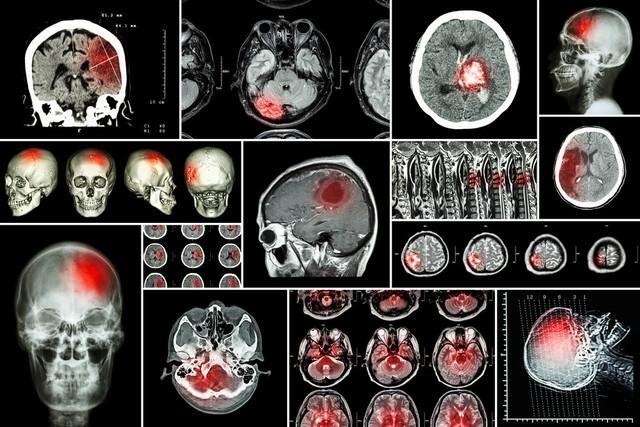

我們的身體猶如一座龐大而精密的城市,血管則是這座城市中錯綜複雜的交通網絡,它們承擔着將血液、氧氣和各種營養物質輸送到每一個細胞和組織的重要使命。而腦梗,恰似這座城市交通網絡中突然爆發的一場可怕的“大堵塞”,瞬間讓血液的流動陷入停滯,進而導致腦組織因缺血、缺氧而遭受嚴重的損傷甚至壞死。